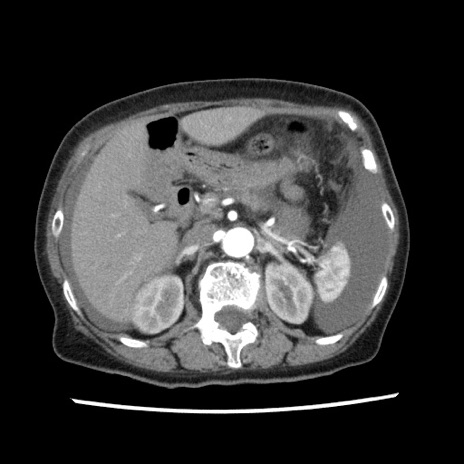

【症例】80歳代女性

【主訴】腹痛

【現病歴】8時間前から腹痛あり来院。

【既往歴】糖尿病、脂質異常症、子宮体癌にて子宮全摘術

【身体所見】意識清明・会話良好だが腹痛で苦悶様、全腹部にわたって反跳痛と圧痛あり

【データ】WBC 13600、CRP 0.14、LDH 224、CK 90